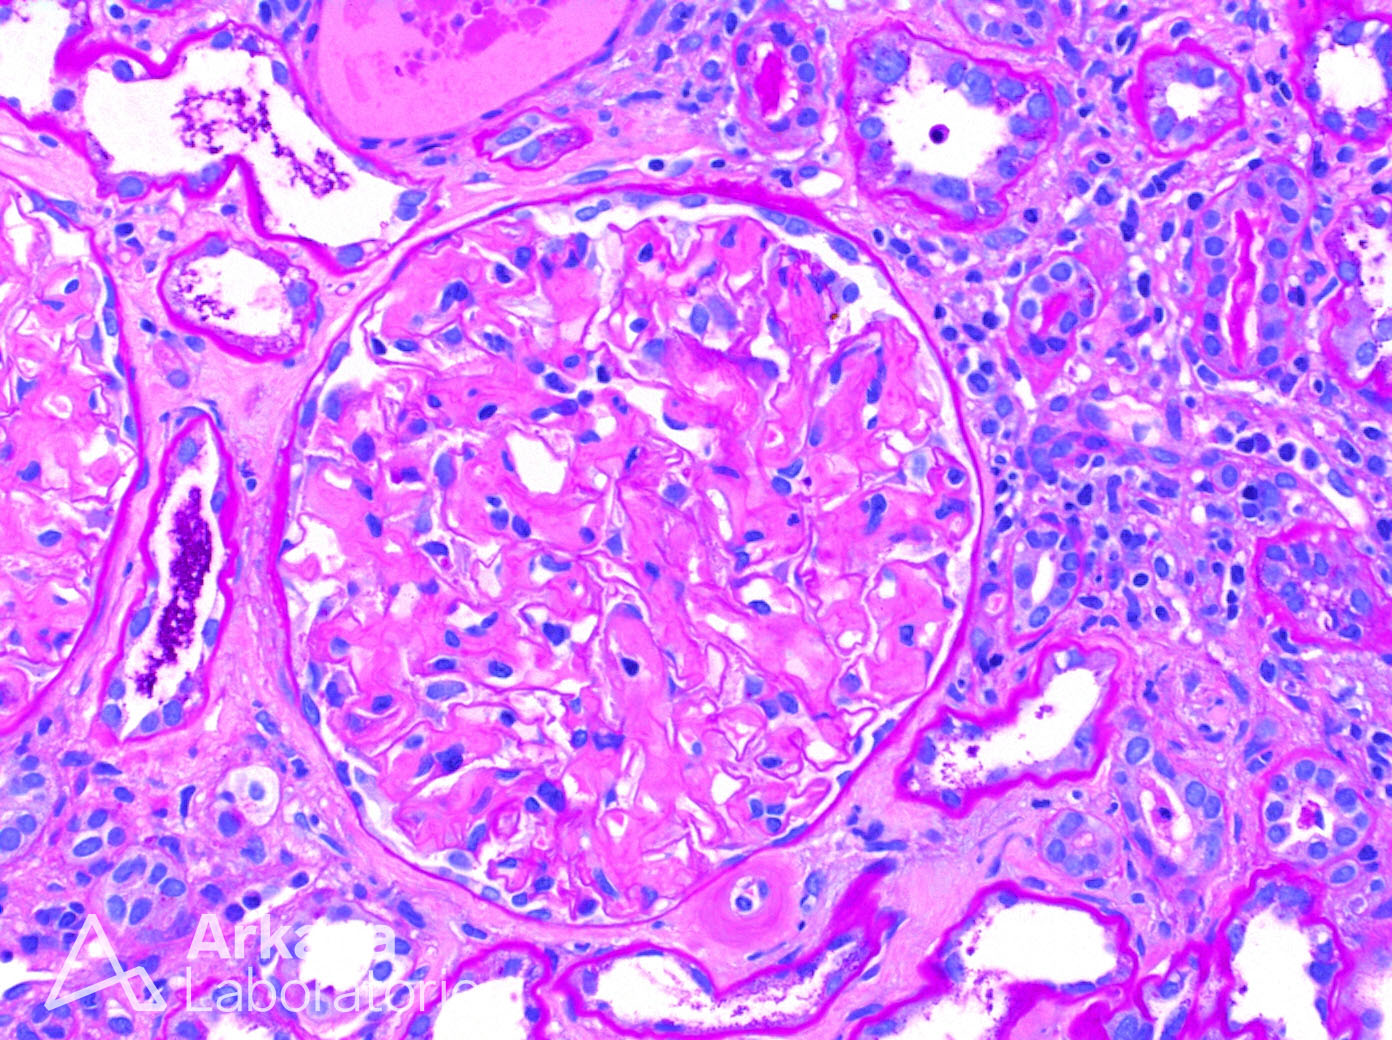

Camera information: Calibration= 1.000 Pixels per pixel; Capture format= 1392 x 1040, Full Frame HQ; Gamma= 0.99; Gain= 1.0 x; Exposure= 8.74 ms; Auto exposure= On; Image type= Colour; Shading= LM; Sharpening= Low; Black clip= 0; White clip= 231;

Microscope information: